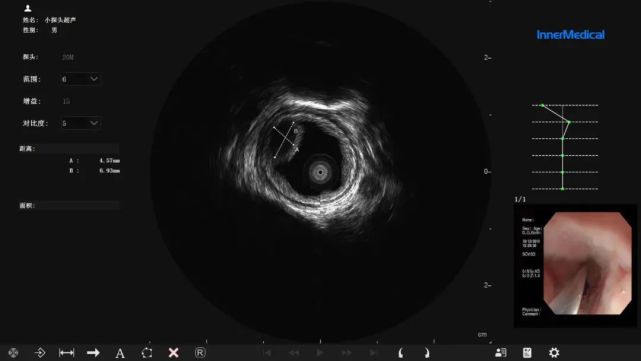

图片

英美达内窥镜超声诊断图像